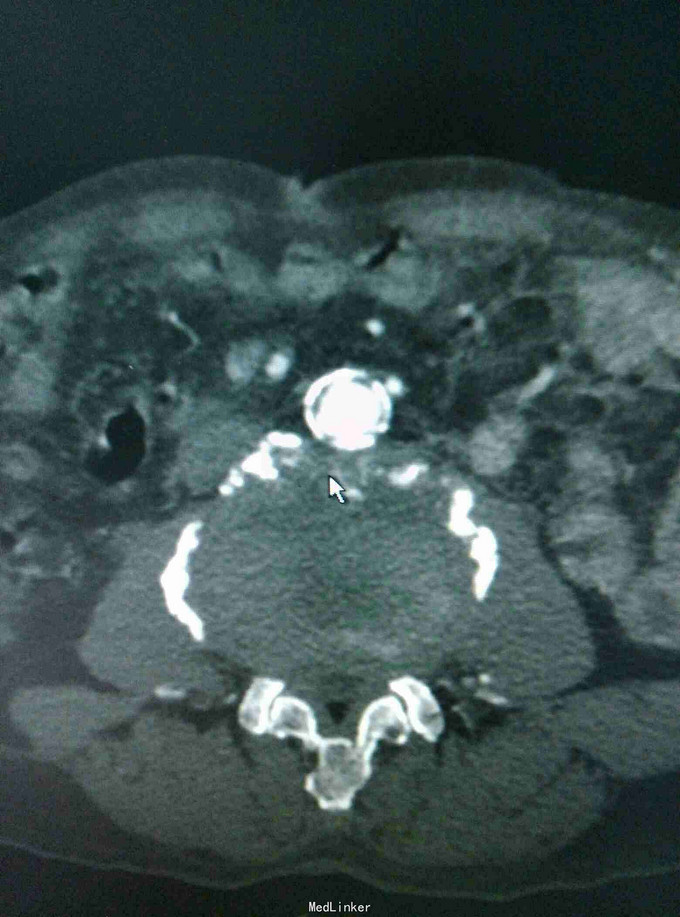

左下肢皮温降低,左足背可见紫红色淤斑,左股动脉扪及微弱波动。下肢血管成像提示:双下肢动脉节段性不同程度狭窄、闭塞。

双下肢动脉硬化闭塞症 手术:左侧髂动脉探查术,术中探查股动脉,导丝导管尝试通过闭塞段髂动脉,但反复尝试无法继续。右侧也无法通过。家属放弃。